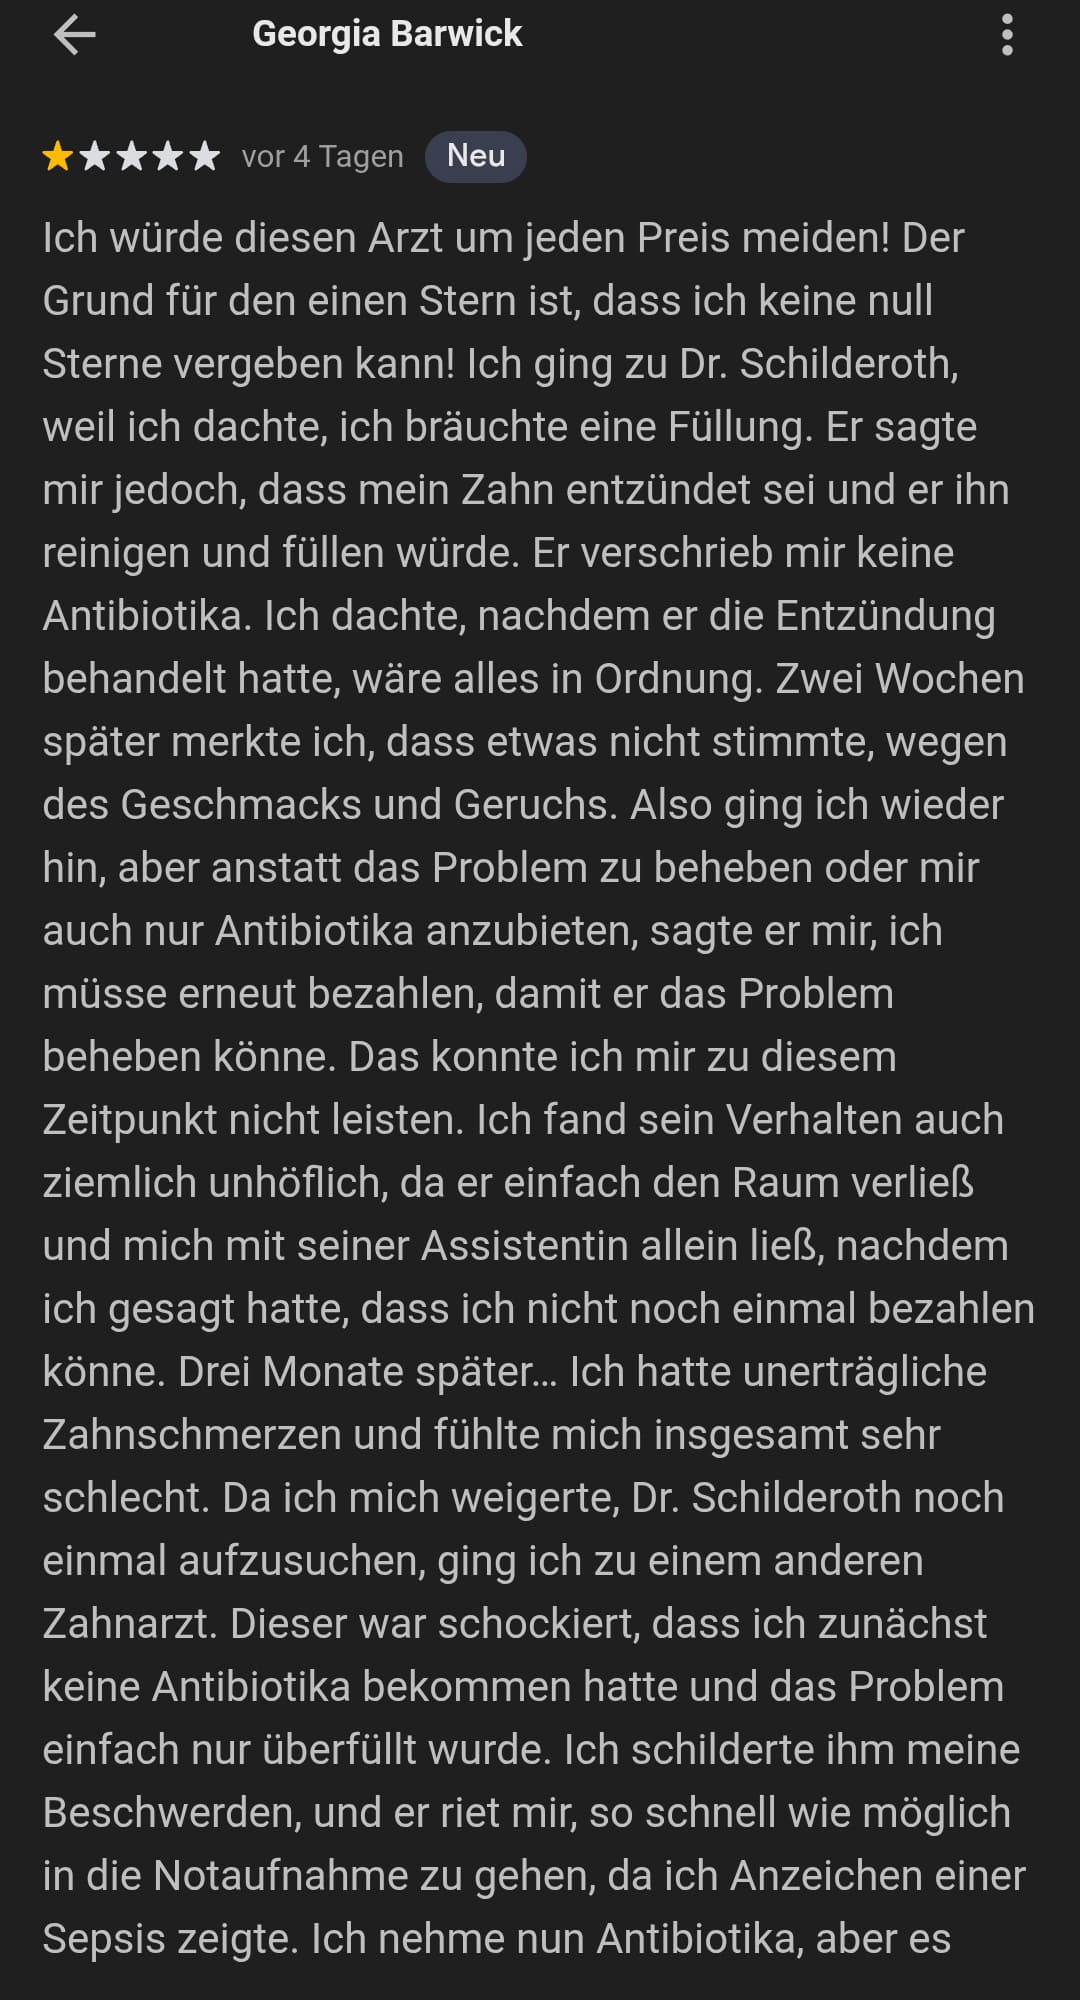

Update 20.12.2025: Doktor Schilderoth Centro Dental hat wieder zwei negative Bewertungen entfernt. Nun ist die Frage, ob beide die Energie und Zeit haben, um Einspruch gegen die Löschung einzulegen. Da ich nichts von Zensur halte, hier die Screenshots von dem Erfahrungsbericht von „Georgia Barwick“ und „Hotel Garden“ über ihre Erfahrung mit Dr. Schilderoth: